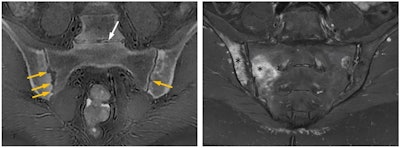

A 39-year-old woman with ankylosing spondylitis. Erosions surrounding the sacroiliac joints (yellow arrows), which are structural lesions pointing to chronic damage, are conspicuously revealed on the CT-like ZTE MR image (left), whereas the STIR MR image (right) superbly shows periarticular osteitis (asterisks) consistent with active sacroiliitis. White arrow showing the L5-S1 intervertebral disk space on the left image points to a pitfall of the ZTE sequence: Gas within joint spaces and soft tissues gives the false appearance of calcifications. Nevertheless, MRI with the ZTE sequence that produces CT-like images affords one-stop imaging in many musculoskeletal conditions obviating the need for additional ionizing radiation-based examinations. Figure courtesy of Üstün Aydingöz, MD, Hacettepe University, Ankara, Turkey.In theory, zero echo time could help to visualize MR imaging of any joint, according to Prince. ZTE sequences are resilient to artifacts caused by motion and magnetic field homogeneities, with great signal-to-noise ratio and scan time efficiencies, and they have advantages in depicting small bone fragments in a trauma setting and subtle cortical erosion.